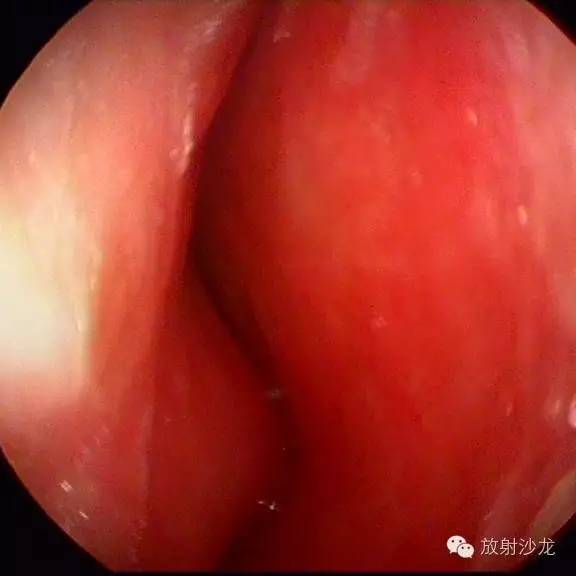

【术前鼻内镜】

术前鼻内镜回报示:左侧鼻腭肿物,鼻中隔偏曲